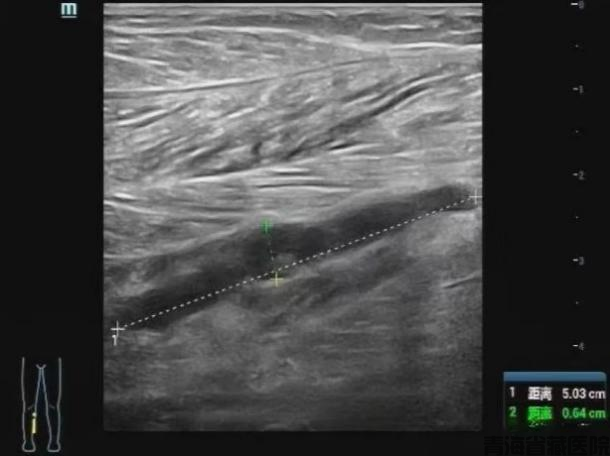

图片3.png

图片4.png

常规二维灰阶超声检查

小腿肌间静脉管腔扩张,充满低回声,探头加压无法压扁,提示血栓形成